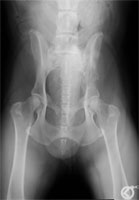

Abb. 11: Becken ventro-dorsal. Bei der Normalbelichtung wird der Knochentumor im Ilium nicht optimal dargestellt.

Abb. 12: Durch digitale Bearbeitung der Bilddatei lassen sich wichtige Bildinformationen individuell herausfiltern.

Abb. 13: Der Knochentumor aus Abb. 11; in der lat.-lat. Ansicht bei Normalbelichtung.

Abb. 14: Durch Korrektur der Helligkeits- und Kontrastwerte erscheinen die dorsalen Beckenstrukturen ¸berstrahlt, die relevanten Bereiche des Ilium mit Weichteilumgebung sind jedoch besser dargestellt.